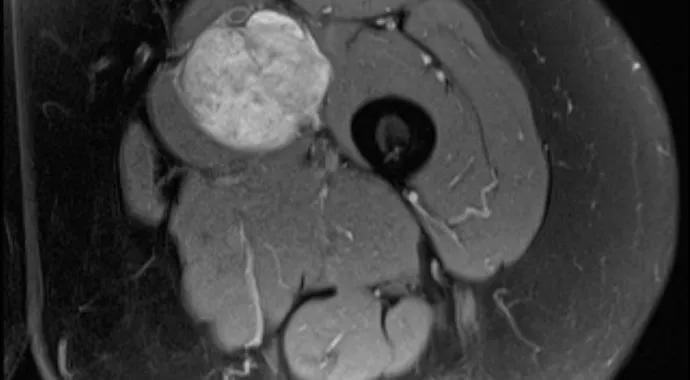

A 62-year-old woman noticed a lump in her thigh. When the tumor did not resolve, she went to her medical doctor, who obtained a CT and referred her to one of the surgeons (S.A.L.) in Cleveland Clinic’s Musculoskeletal Tumor Center. The patient had severe claustrophobia, so she underwent MRI under anesthesia. In addition, a deep vein thrombosis was discovered at the area of the tumor, so an inferior vena cava filter was placed. She was started on enoxaparin but could not tolerate the injections, so she was switched to aspirin, 325 mg twice daily. Based on the MRI findings (Figure), her lesion was believed to be a leiomyosarcoma of the femoral vein, which was confirmed by a minimally invasive needle biopsy.

Figure. Axial (left) and coronal (right) MRIs showing the leiomyosarcoma in the left thigh arising from the femoral vein.